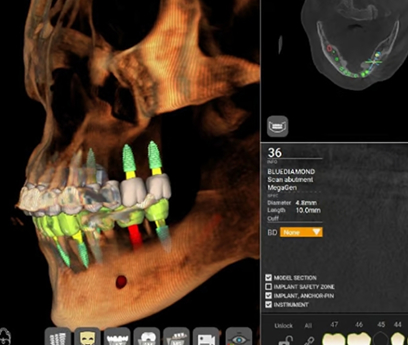

В нашей клинике используется цифровая система планирования, что позволяет точно спланировать место установки каждого импланта, минимизировать хирургическое вмешательство и сразу же установить индивидуальные протезы.